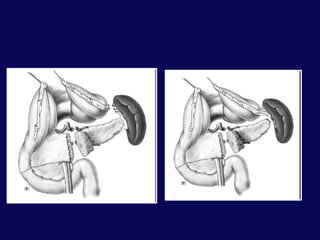

Tamir koruma“Triple” tubeLateral duodenostomiRetrogradeDuodenal DivertikülizasyonPilorik Ekslüzyon

Kombine Pankreatikoduodenal YaralanmalarPrimer duodenal onarımPankreatik drenajDuodenal dekompresyon              Üç tüp dekompresyonu              Gastrostomi ve duodenostomi              Duodenal divertikülizasyon